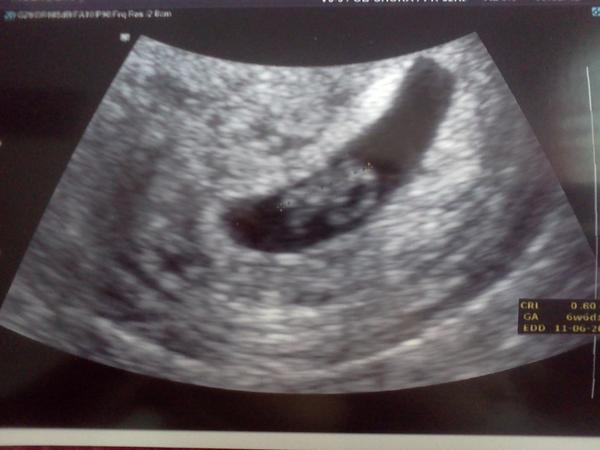

@verul2 To je pecka uuuuzasny! Moc gratuluju, fotecka vypada fantasticky teda 😉 Ja jdu pristi tyden v patek a uz se nemuzu dockat, doufam, ze budu mit taky takove dobre zpravy a krasnou fotecku. A vypocitali ti uz ted termin? Ja bych mela byt podle PM 7+2, uvidime teda na kontrole, odhaduju 6+2, jelikoz ovu myslim byla o tyden pozdeji. Kazdopadne to budeme kousek od sebe 😉 Preju spoustu zdravicka, at fazolka jenom roste 😉

@verul2 Ahojky, tak se hlasim po kontrole. Vsechno v poradku a je tam kde ma, velikostne 3 mm, terminove dle PM 8+2, ale dle utz cca 6, tak uvidime, jak porosteme. Fotecku nemam, neb bylo to neco namuchlane uplne v rohu, ze sem to ani nepoznala. Nastesti doktor jo, i se srdickem, tak uvidime za tri tydny na prvnim screeningu. 😉